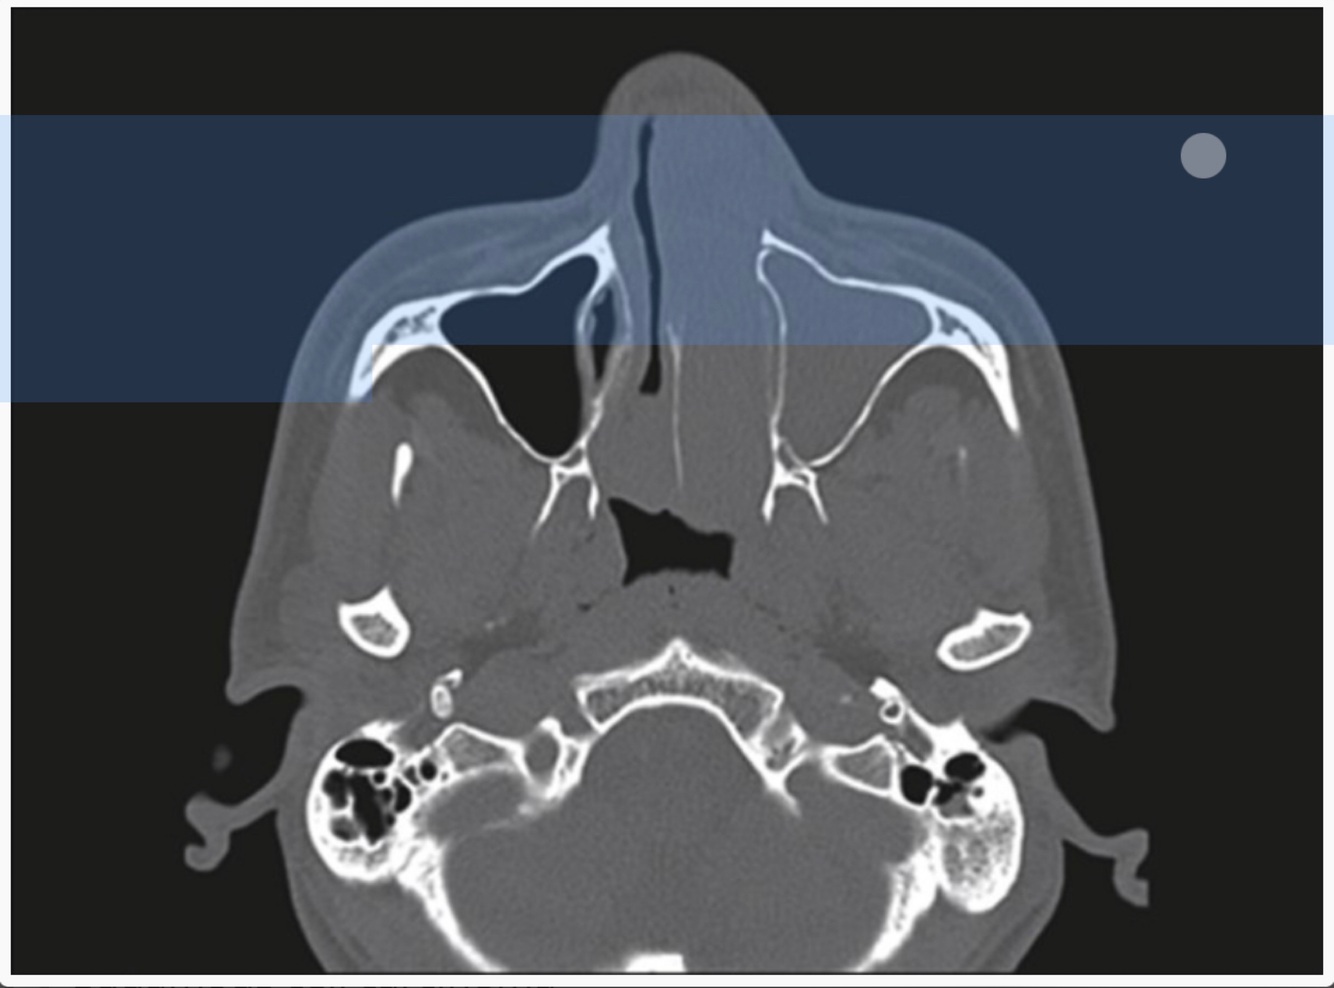

A 69-year-old female presents with nasal obstruction, facial pressure and discolored nasal drainage for 4 months that is recalcitrant to topical steroid sprays, nasal irrigations, and oral antibiotics.

Diagnosis?

A

Inverted papilloma with a bony stalk attaching near the infraorbital nerve

What next step would assist in diagnosis?

A biopsy is warranted to confirm the diagnosis, w/use of a bioendoscopy filter.

12

Q

CT of paranasal sinuses reveals erosion or expansion into

lateral nasal wall or extension into maxillary or ethmoid sinuses, and may reveal calcifications.

Inverted Papilloma.

CT/CTA/MRI/MRA of paranasal sinuses, shows a mass with extension into the pterygomaxillary fissure.

Dx?

JNA